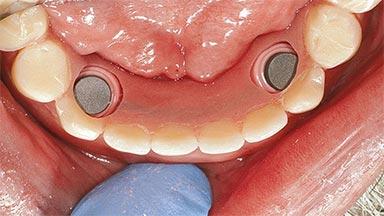

# of Implants 2

Type of Implants One-Piece

Attachment One-Piece